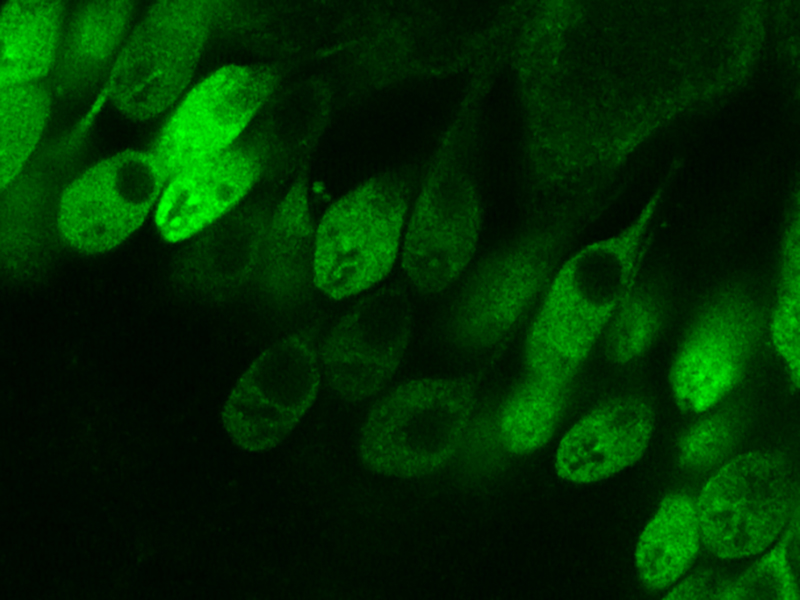

My research has centered on understanding the underlying cellular mechanisms and identifying novel treatments for neurodegenerative, neuromuscular, and inflammatory diseases. Most recently, I have been developing gene therapies for diseases that affect the eye like retinitis pigmentosa, uveitis, and age-related macular degeneration.

Earlier in my career I studied muscular dystrophies associated with mutations in dysferlin and members of the dystrophin-glycoprotein complex. While these are very different diseases from those that affect the eye, the underlying cell biology share common features. For example, inherited mutations can have a negative consequence on calcium signaling, cell membrane biology, or cytoskeletal dynamics, which ultimately cause different diseases depending on the cell type affected (i.e. muscle myofibers or retinal neurons).